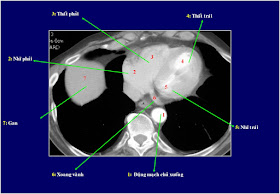

Chụp cắt lớp vi tính (CLVT) phổi và lồng ngực đánh giá được tình trạng bệnh lý của xương sườn, màng phổi, nhu mô phổi, phế quản, tim, mạch máu, trung thất…. Dựa vào hình ảnh chụp CLVT có thể nhìn thấy những bất thường mà không thể phát hiện dễ trên phim chụp X quang tiêu chuẩn thẳng hoặc nghiêng vì bị các tạng khác chồng lên che khuất.

Để có thể chẩn đoán được cần biết rõ về cấc mốc giải phẫu trên cấc lát cắt.